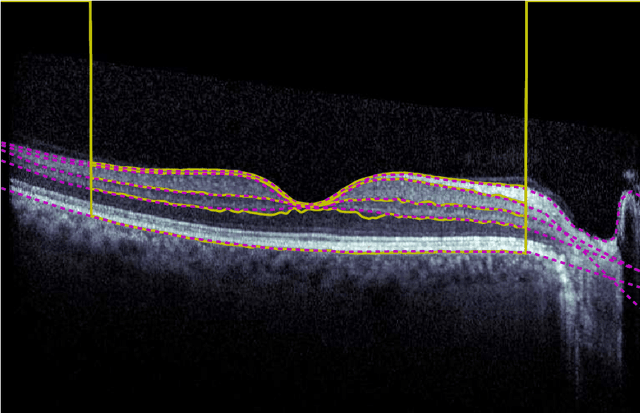

Abstract:Our objective is to evaluate the efficacy of methods that use deep learning (DL) for the automatic fine-grained segmentation of optical coherence tomography (OCT) images of the retina. OCT images from 10 patients with mild non-proliferative diabetic retinopathy were used from a public (U. of Miami) dataset. For each patient, five images were available: one image of the fovea center, two images of the perifovea, and two images of the parafovea. For each image, two expert graders each manually annotated five retinal surfaces (i.e. boundaries between pairs of retinal layers). The first grader's annotations were used as ground truth and the second grader's annotations to compute inter-operator agreement. The proposed automated approach segments images using fully convolutional networks (FCNs) together with Gaussian process (GP)-based regression as a post-processing step to improve the quality of the estimates. Using 10-fold cross validation, the performance of the algorithms is determined by computing the per-pixel unsigned error (distance) between the automated estimates and the ground truth annotations generated by the first manual grader. We compare the proposed method against five state of the art automatic segmentation techniques. The results show that the proposed methods compare favorably with state of the art techniques, resulting in the smallest mean unsigned error values and associated standard deviations, and performance is comparable with human annotation of retinal layers from OCT when there is only mild retinopathy. The results suggest that semantic segmentation using FCNs, coupled with regression-based post-processing, can effectively solve the OCT segmentation problem on par with human capabilities with mild retinopathy.